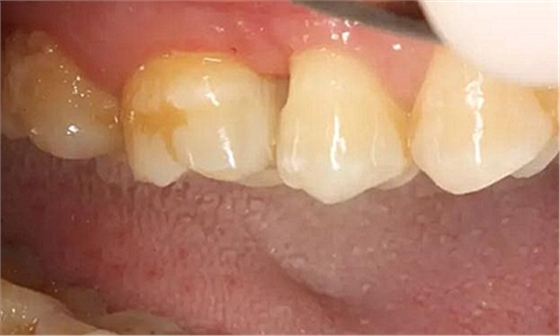

患者男性,35歲,B6銀汞充填后食物嵌塞,要求重新充填,口內(nèi)檢查見B6近中鄰頜面銀汞充填物,局部缺損,有繼發(fā)齲,去除原充填物及繼發(fā)齲,發(fā)現(xiàn)齲壞位于牙齦下方,給予冠延長手術(shù),同期嵌體預(yù)備,后一次性取模。(同樣設(shè)計(jì)為齦上邊緣)

硅橡膠取模后,灌注模型,科爾琥珀樹脂制作嵌體。

一周后拆線,口內(nèi)試戴合適,粘結(jié)嵌體。